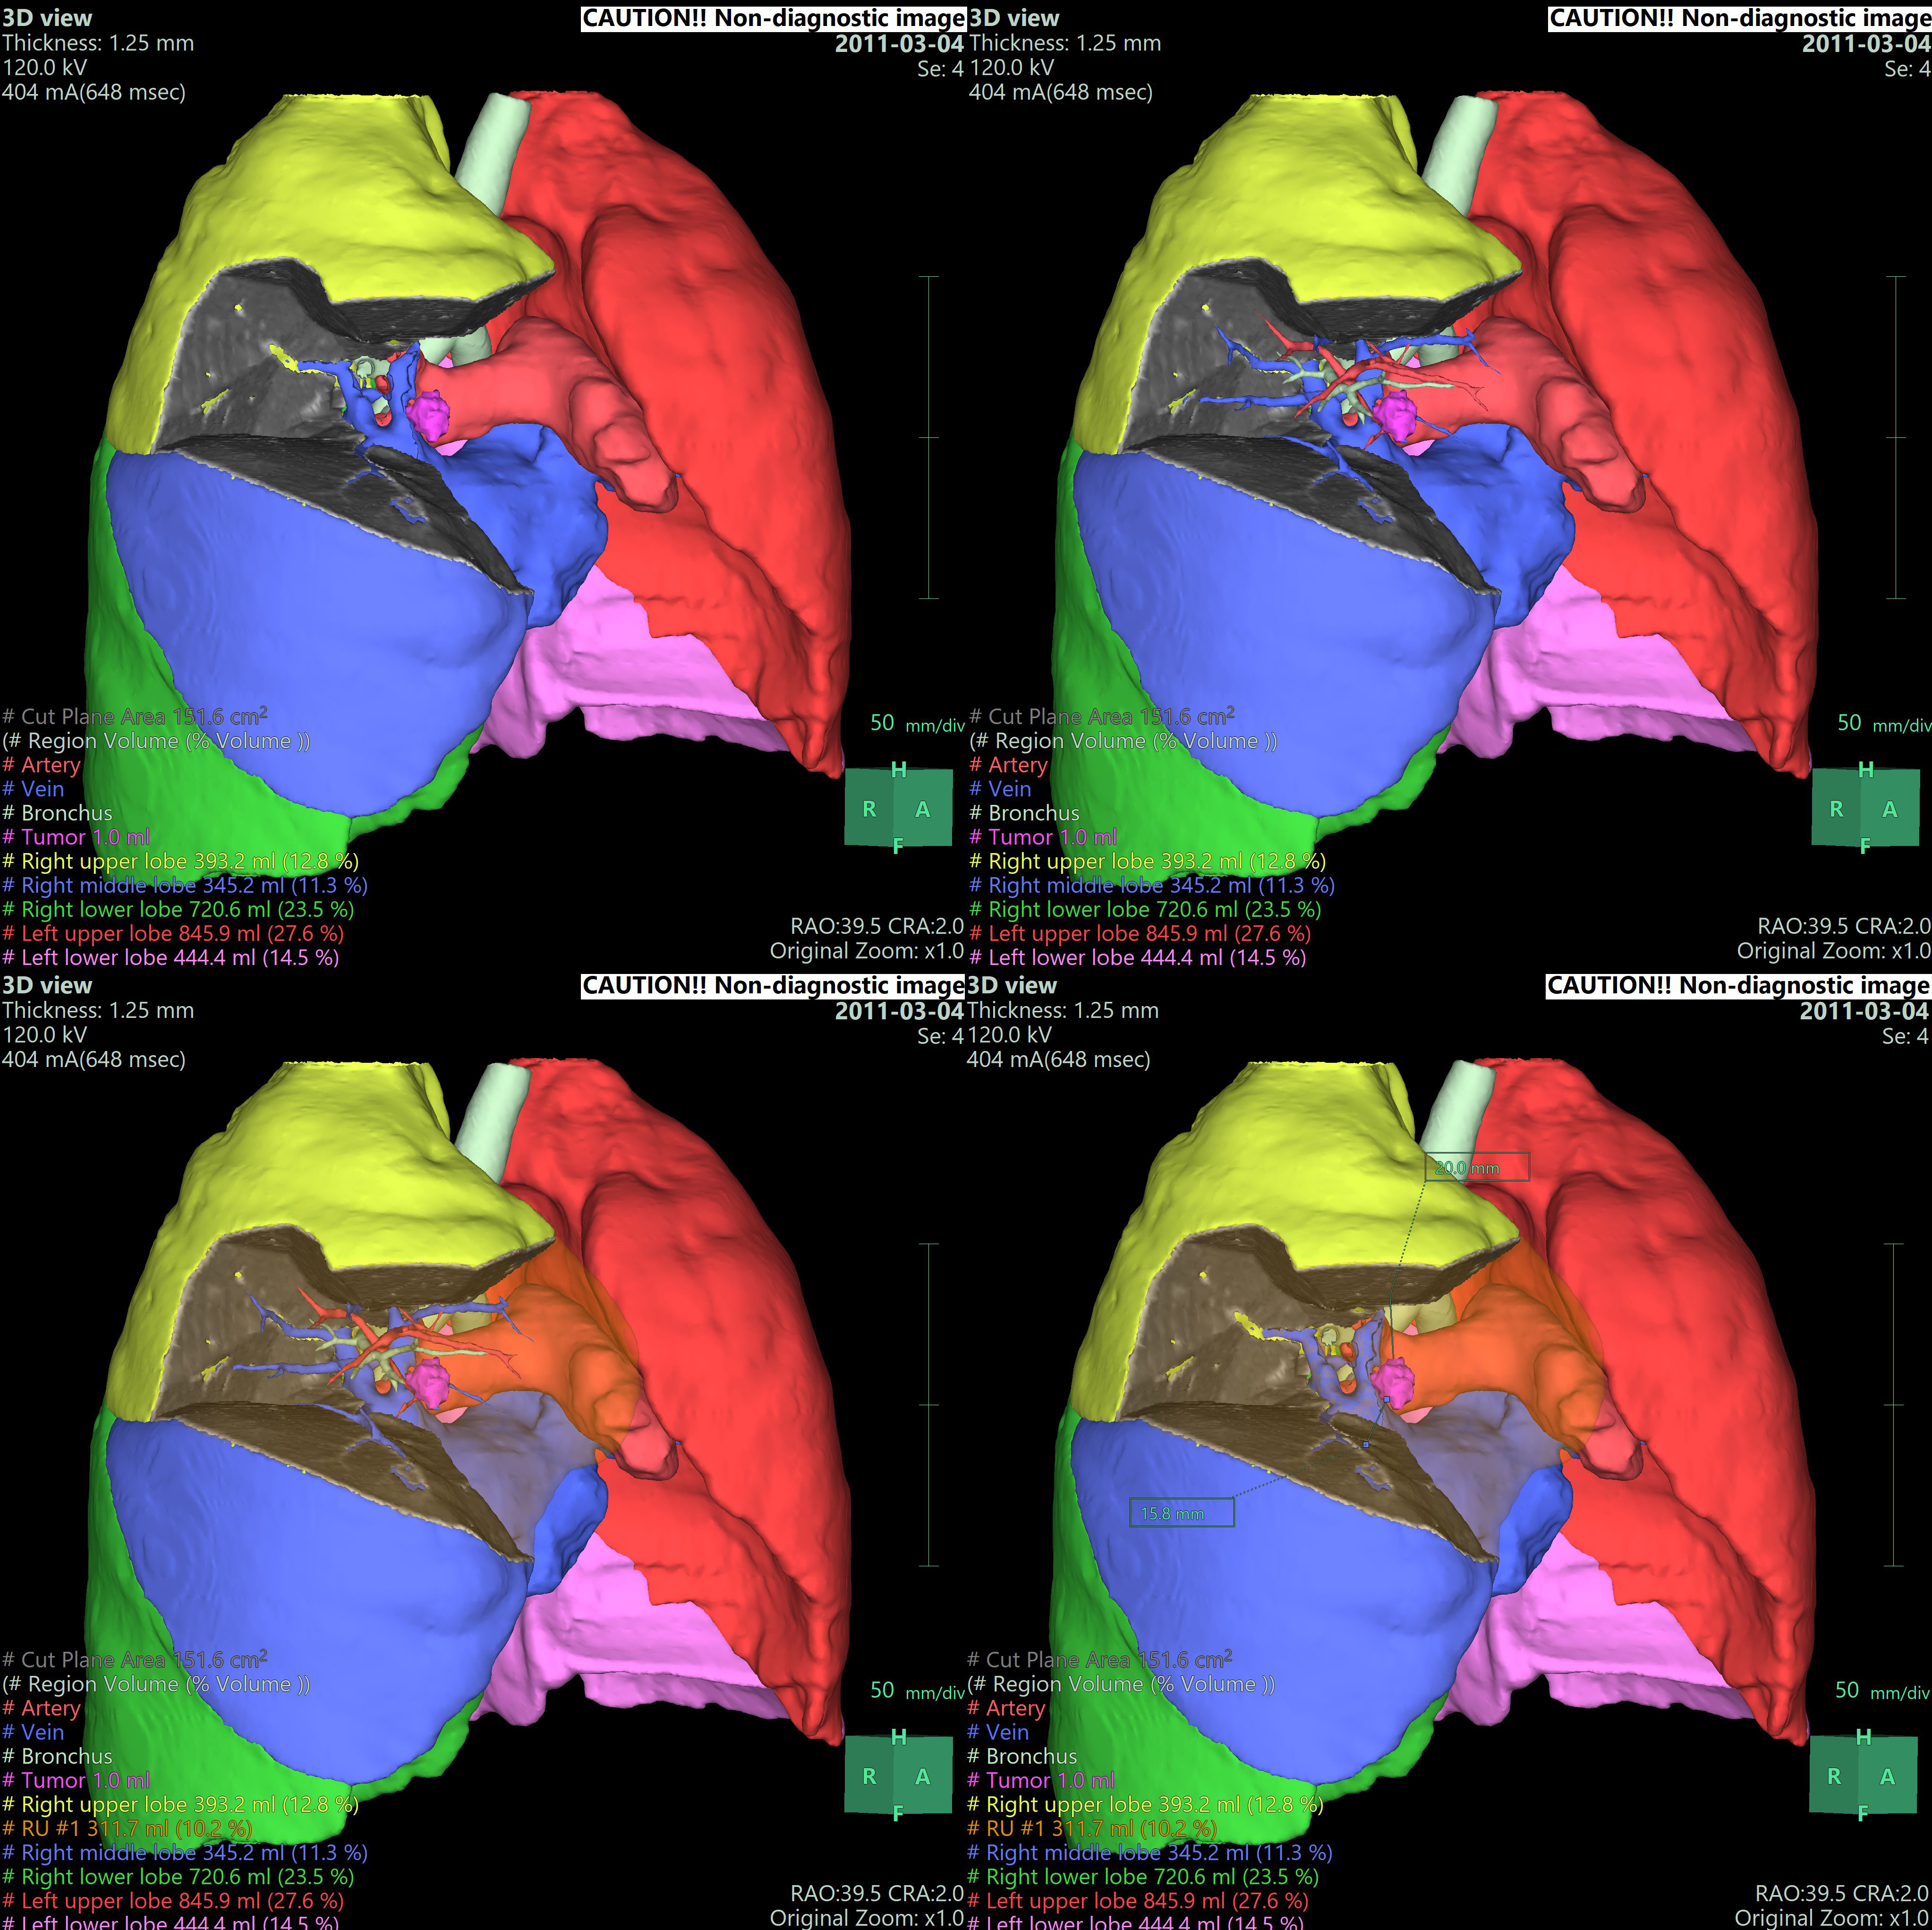

• - 임의의 Vascular point에서 territory를 분리하고 절제면, 절제면에서의 Vessel 및 territory의 volume 등을 측정할 수 있습니다.

• - 영역을 분리하고 tumor에서 plane 까지의 최소거리를 자동으로 측정할 수 있습니다.

• - 조영 증강된 CT image를 사용하여 Lung, Airway, Vessel, tumor 등을 추출하고 3D로 재구성하고 결과를 관찰할 수 있습니다.